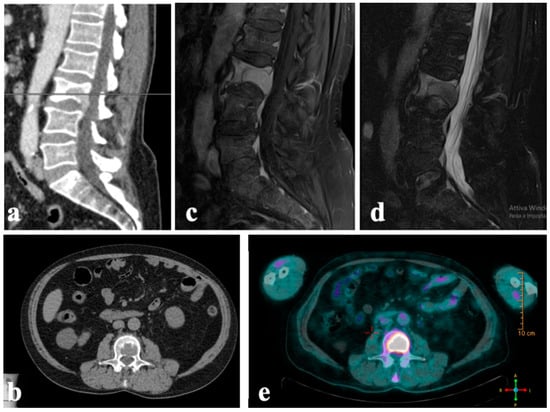

4. Case Series